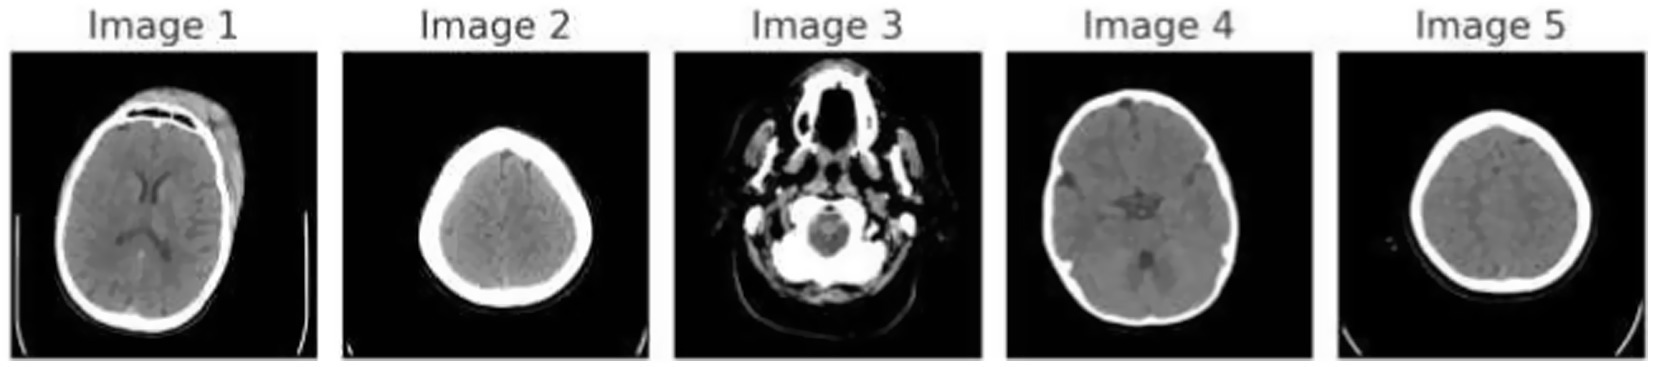

Figure 1 demonstrates the unprocessed and processed CT scan brain scans. Raw images are initially scanned, whereas the processed ones have undergone a procedure of removing noise and normalization to facilitate analysis. Figure 2 shows grayscale, equalized, and edge-detected images of the preprocessed brain images. Gray levels eliminate color, equalization increases contrast, and edge detection emphasizes boundaries of key structures. The CT scan cross-sections shown in Figure 3 are used to obtain details about brain structure and the parts prone to abnormalities such as strokes and tumors. Figure 4 shows different CT scan cross-sections with varying types of stroke, and how ischemic and hemorrhagic strokes can be represented in the brain in a cross-section.

Figure 1

Dataset overview: raw and processed brain CT scan images.